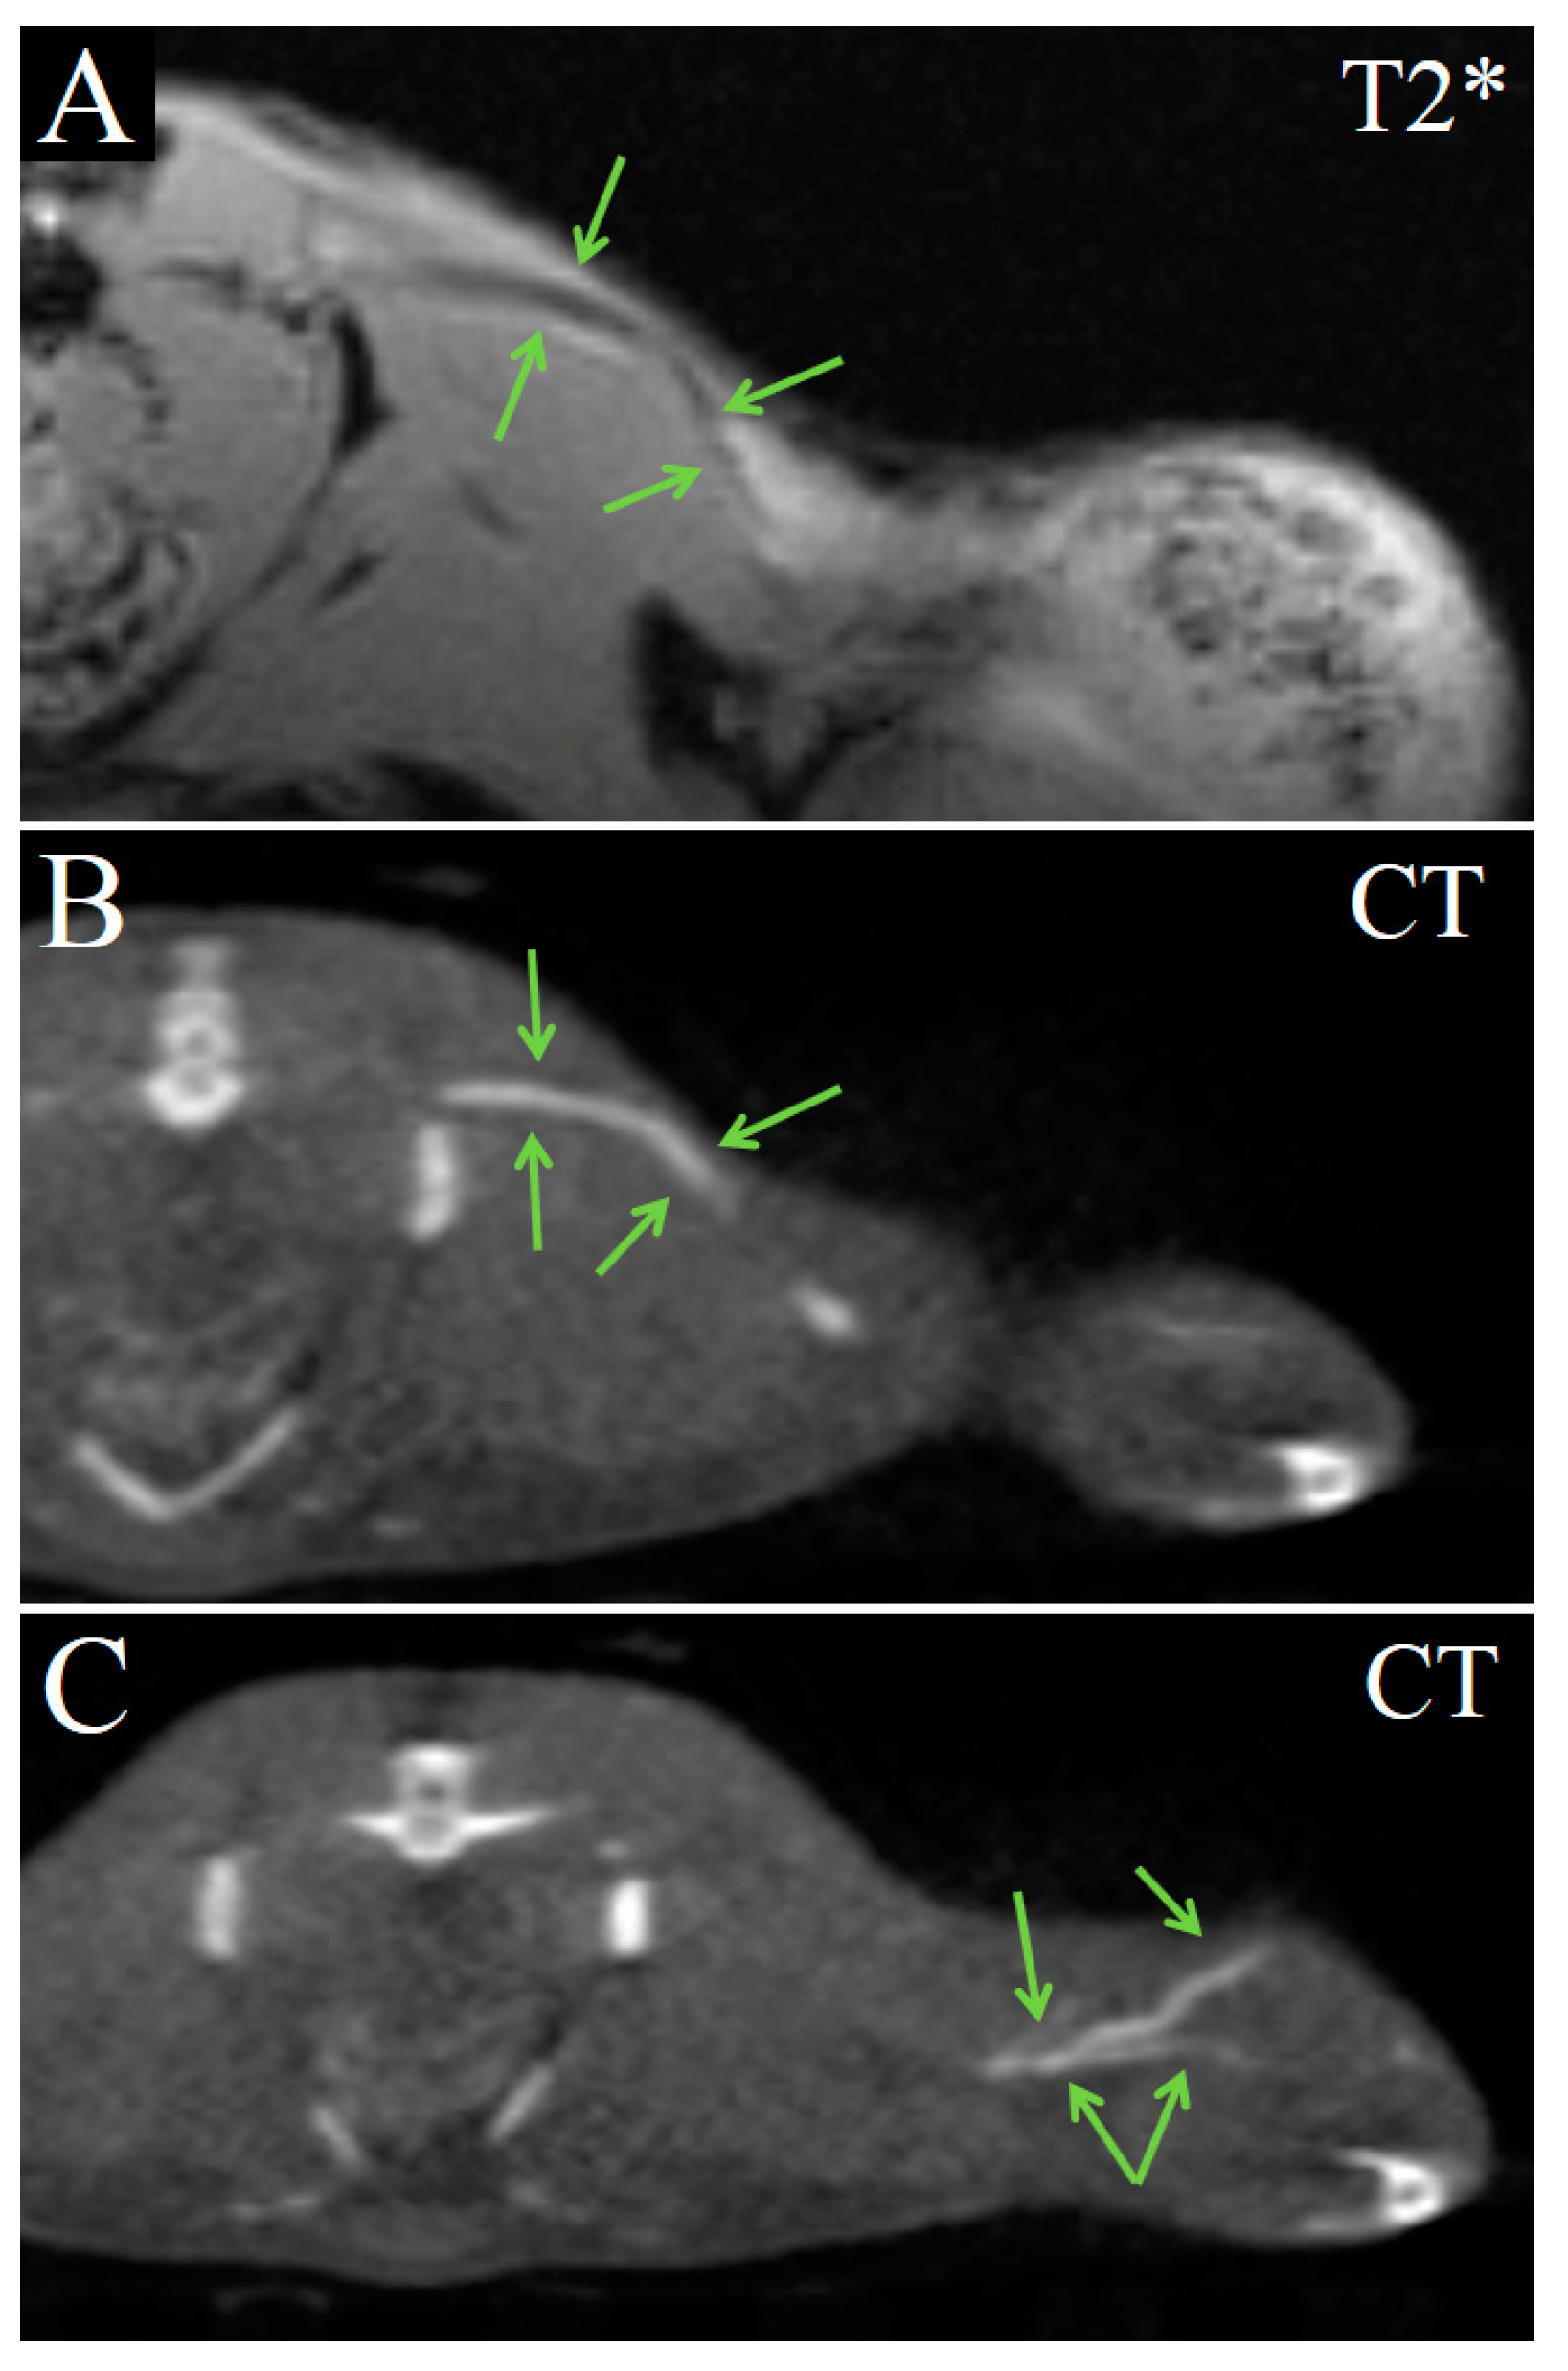

2. Results